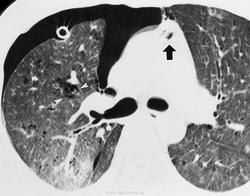

Пациент, будучи в нетрезвом состоянии взял паракват в рот, и затем выплюнул.

Отравления при вдыхании параквата.

Паракват - это гербицид, который используется в сельском хозяйстве во многих странах.